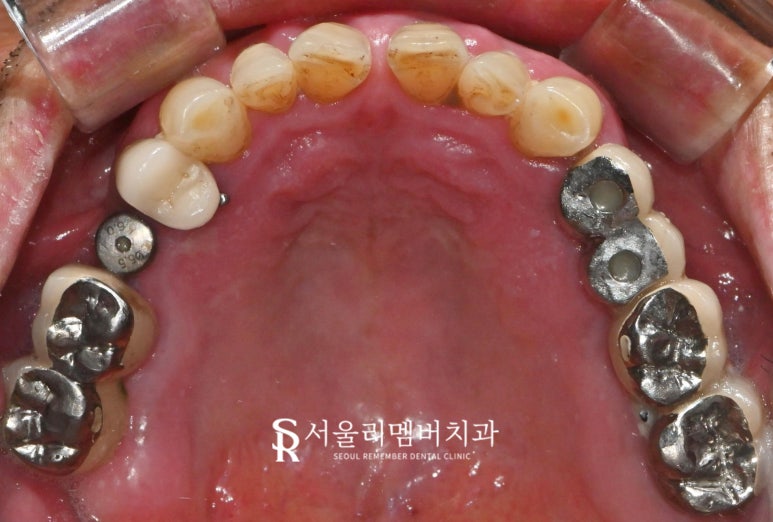

얼마 전 내원하셨던 분은 하악 어금니 부위에

#45부터 #47까지 브릿지를 사용 중이셨는데,

치아에 불편함이 있고 통증이 느껴진다는

주소로 내원하셨습니다.

오랜 기간 사용해온 브릿지가

치은 퇴축으로 인해 마진이 드러나게되어

불편감을 초래하고 계셨어요.

환자께서는 검진을 받으신 지 꽤 오래되어

추가로 전체 구강 검진을 시행했는데요,

결과를 보던 중 다른 문제점도

발견되어 정밀 검사를 진행했습니다.

서울대입구역 치과 에서는 엑스레이 검사를 통해

환자의 구강 상태를 다음과 같이 확인했습니다.

#45, #47 치은 퇴축 및 마진 드러남

기존 bridge 부위는 치은 퇴축으로 인해

마진이 보여지게되어 재수복이 필요했습니다.